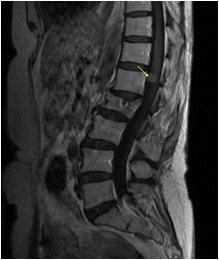

We found a strong positive correlation between abnormal EEG and abnormal Neuroimaging with Correlation coefficient of 0.902, (P- Value 0.0138) but almost no correlation found between normal EEG with normal Neuroimaging (Figs 1-4).

About 23% of patients with adult onset first seizure has metabolic derangement and the most common etiology was Dyselectrolytemia. The most common Central Nervous System (CNS) Infection as detected by CSF study was viral meningoencephalitis followed by Tuberculous Meningitis. The most common CNS lesion detected by CT studies as well as by MRI Brain was infarction and ring lesion, the two Neuroimaging studies corroborated in 75.38% of Seizure patients. Abnormal discharge in EEG found in34% cases. In majority patients EEG report was normal. EEG abnormality was more common in patients with Focal Seizure rather than GTCS patients. Thus, the most common etiology of first Seizure onset at adult age over 18 years were metabolic derangements (16.92%), CNS Infection or Inflammation (15.38%) and intracerebral Space occupying lesion (15.38%), usually ring lesion, tumors and Metastasis. Idiopathic Seizure found in 7.69% patients. The Correlation between abnormal Neuroimaging and abnormal EEG is strongly positive and statistically significant (P -Value = 0.013) but the same is not true in cases of normal Neuroimaging and normal EEG findings.